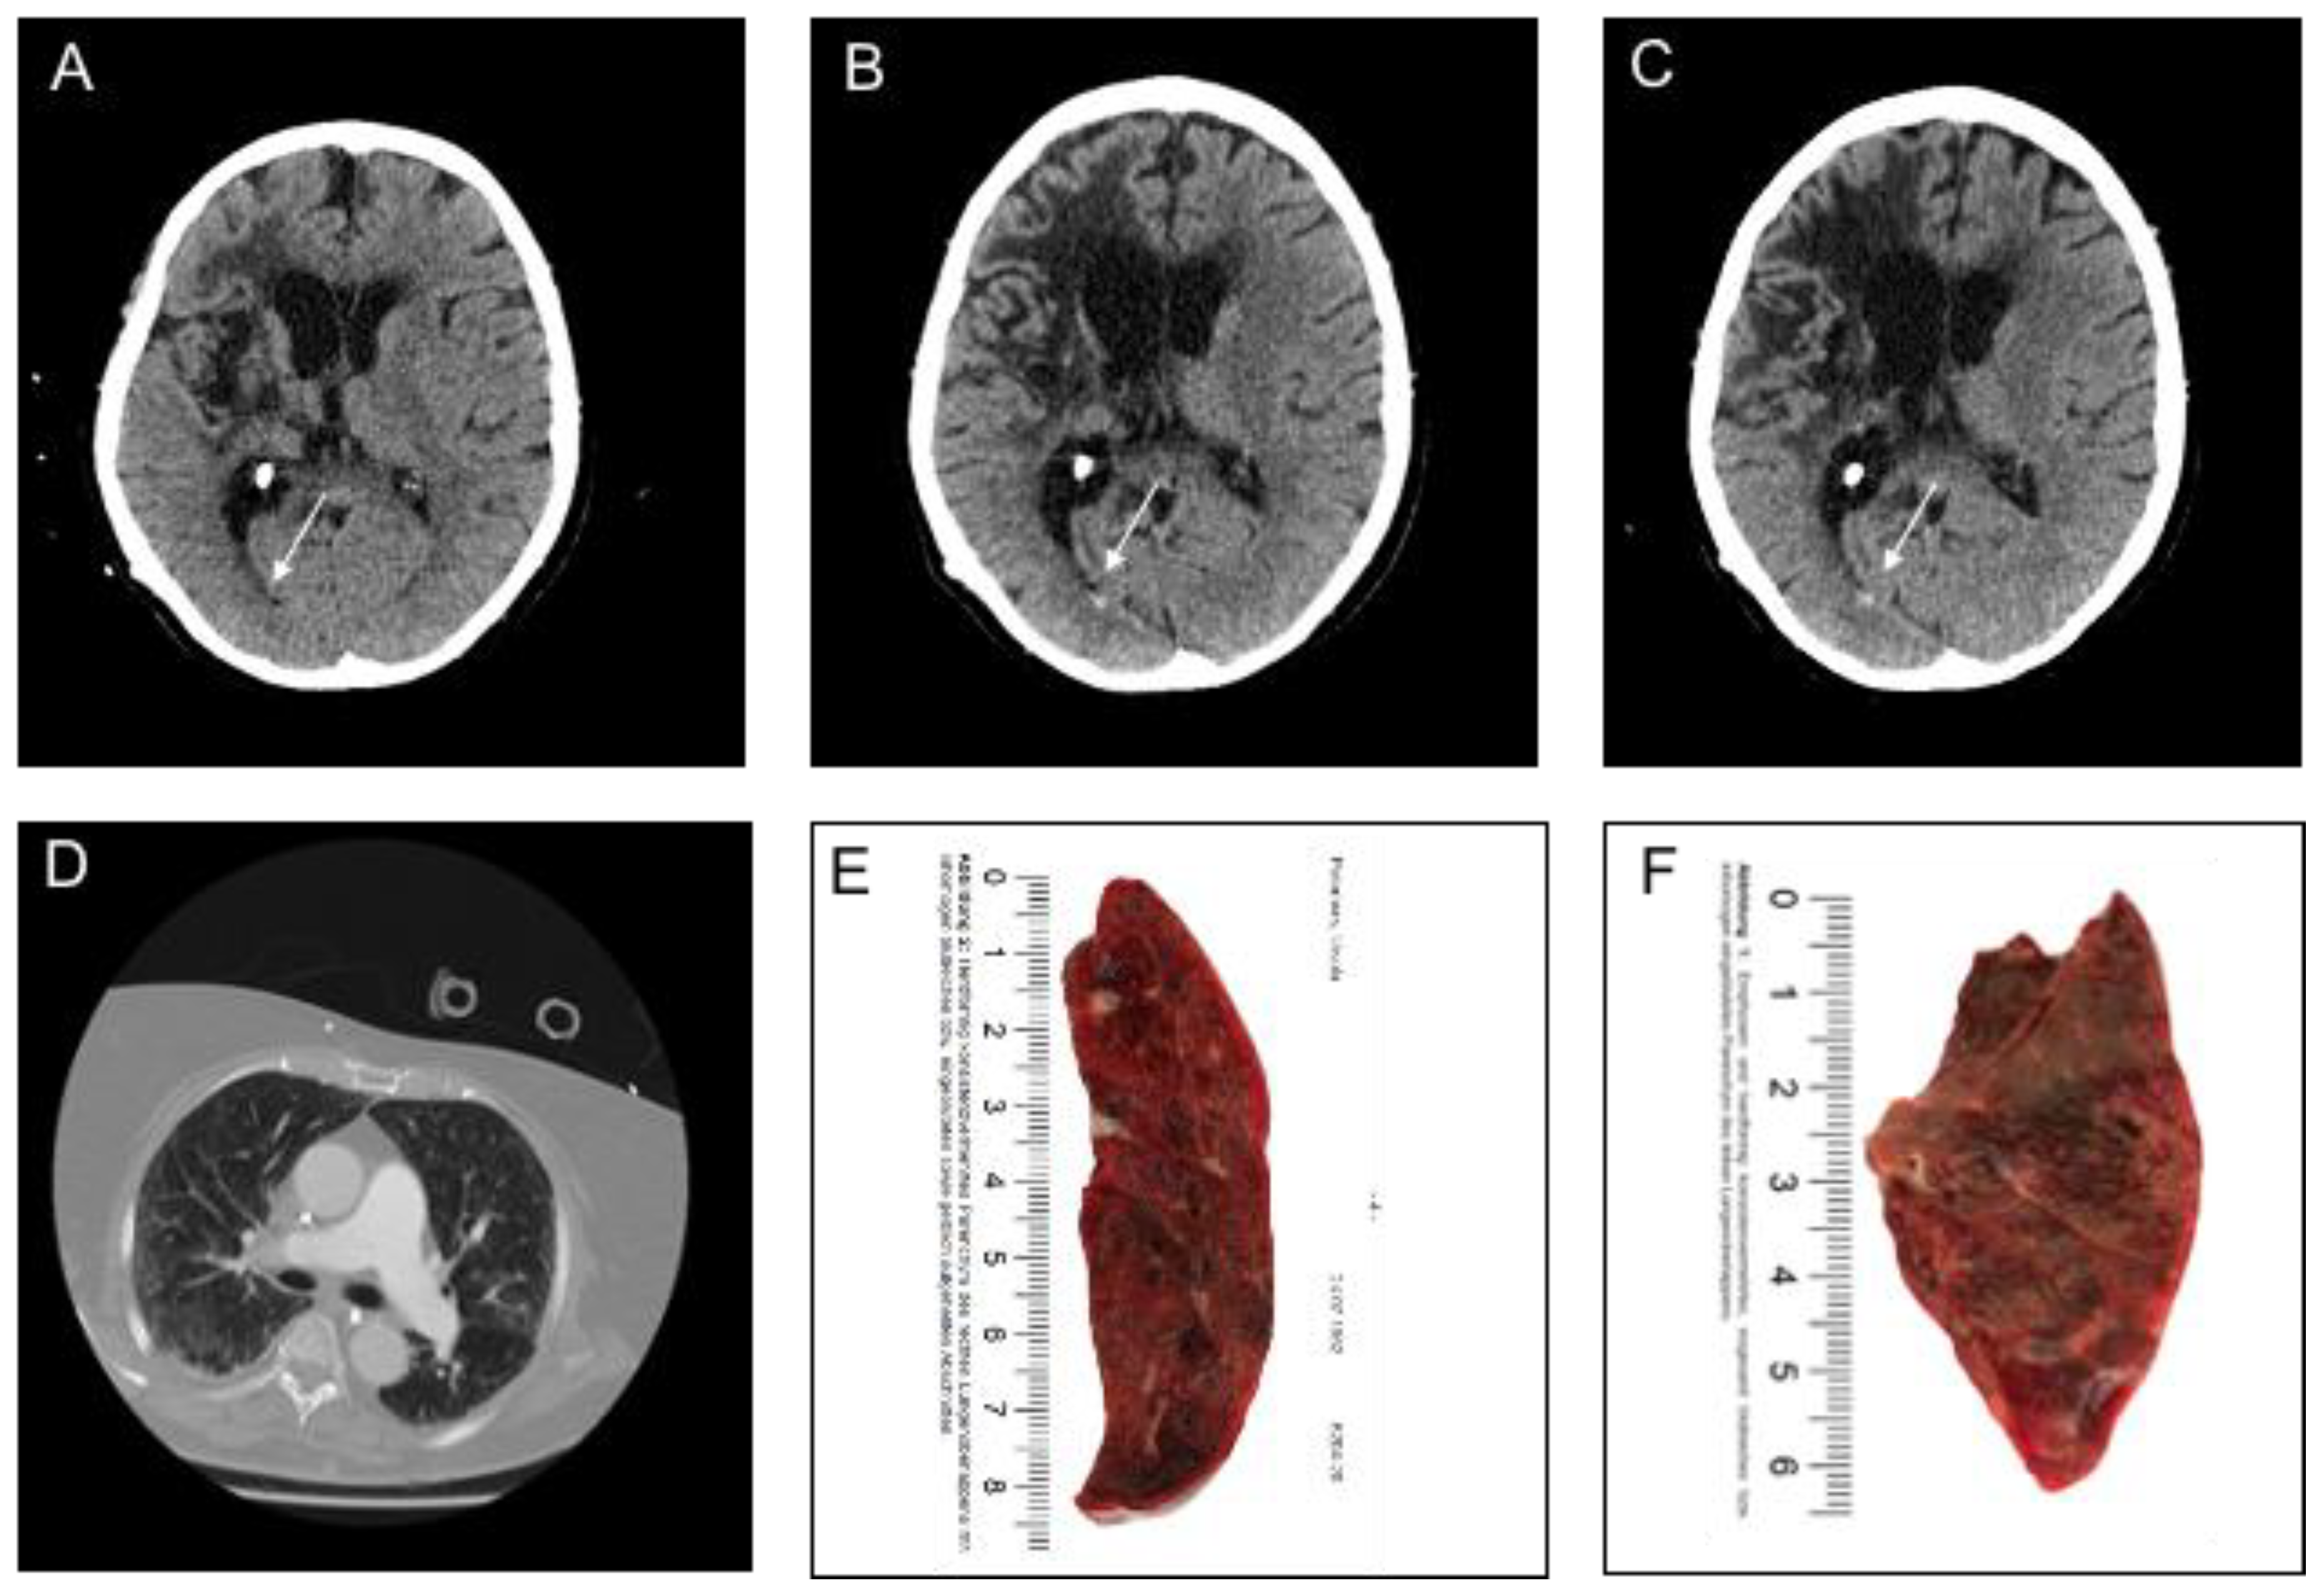

3.2. Imaging and Clinical Findings

| Parenchymal Hemorrhage (n = 6) | |

| Location | |

| • Lobar, n (%) | 4 (66.7) |

| • Deep, n (%) | 1 (16.7) |

| • Infratentorial, n (%) | 1 (16.7) |

| Ventricular extension, n (%) | 1 (16.7) |

| SAH extension, n (%) | 1 (0) |

| Subarachnoid Hemorrhage (n = 11) | |

| Primary SAH, n (%) | 9 (81.8) |

| • Aneurysmal, n (%) | - |

| • Cortical, n (%) | 9 (81.8) |

| • Bilateral, n (%) | 4 (36.4) |

| • Ventricular extension, n (%) | - |

| Secondary SAH, n (%) | 2 (18.2) |

| Intraventricular Hemorrhage (n = 3) | |

| Isolated IVH | |

| • Supratentorial, n (%) | 3 (100) |

| • Infratentorial, n (%) | - |

| • SAH extension, n (%) | - |

| Secondary IVH *1, n (%) | 1 (33.3) |

| Subdural Hemorrhage (n = 1) | |

| Convexity, n (%) | 1 (100) |

| Bilateral, n (%) | - |

| SAH extension, n (%) | 1 (100) |